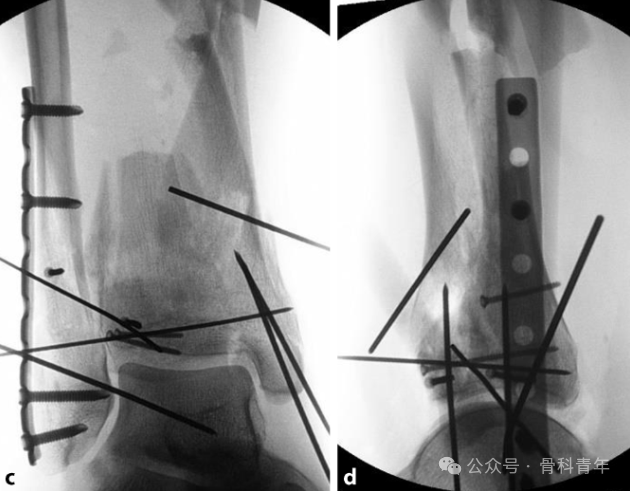

固定(Span):实施跨关节外固定架固定术;